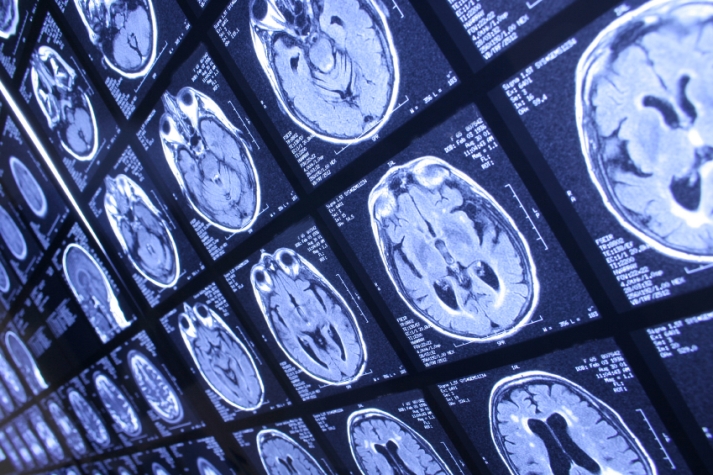

Believing that improving brain health takes “massive collaboration”, the Ontario Brain Institute today launched the province’s first Neuroscience Asset Map. The map will connect over 800 researchers with hospitals, neurological charities, ‘brain companies’, patients and the public.

The Asset Map is an online tool with a growing database that lists virtually every brain-related resource in the province. Users can access the tool and find neuroscience expertise and talent ranging from researchers studying Alzheimer’s disease to companies developing neurotechnologies to patient advocacy groups supporting those suffering from a major brain disorder.

If users want to know which researchers have experience in imaging, or which companies produce medical devices, the Asset Map will provide that information. The map is free and anyone can use it and offer feedback. Anyone can request the addition of new researchers or organizations to the database.